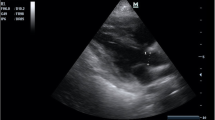

The LVOTd was measured from a parasternal long-axis view (Fig. 1). The distance from the inner edge to inner edge of the LVOT was measured in a line parallel to the aortic annulus from the base of the right aortic valve coronary cusp to the base of the non-coronary cusp. The VTI was measured by obtaining an apical 5-chamber view and then placing a pulsed-wave Doppler cursor in the LVOT below the aortic valve annulus (Fig. 2). We measured the VTI, at the same time, in the respiratory cycle, ideally at the end of expiration.